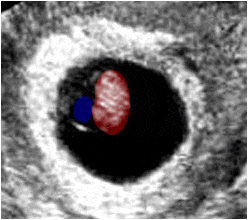

Ecografía obstétrica que muestra, en un corte transversal de utero, un saco gestacional de 7 semanas. En su interior se observa una zona ecorrefringente que corresponde a la imagen del embrión (rojo), y una zona econegativa que corresponde al saco vitelino (azul).